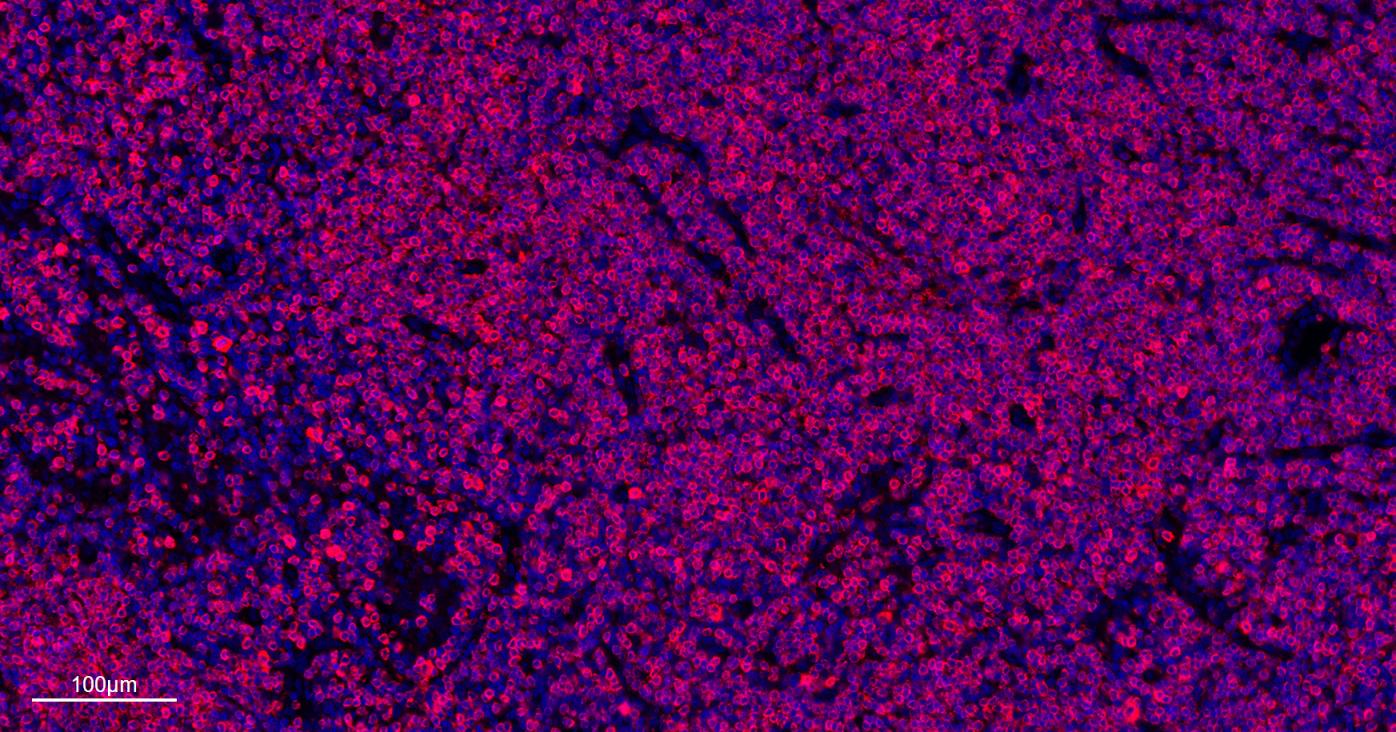

Paraformaldehyde-fixed, paraffin embedded Mouse Thymus; Antigen retrieval by boiling in sodium citrate buffer (pH6.0) for 15 min; The section was incubated with CD3E Monoclonal Antibody, Unconjugated (bsm-60002) at 1:500 overnight at 4°C. Followed by conjugated Goat Anti-Rabbit IgG antibody (Red, bs-0295G-BF594), DAPI (blue, C02-04002) was used to stain the cell nuclei.